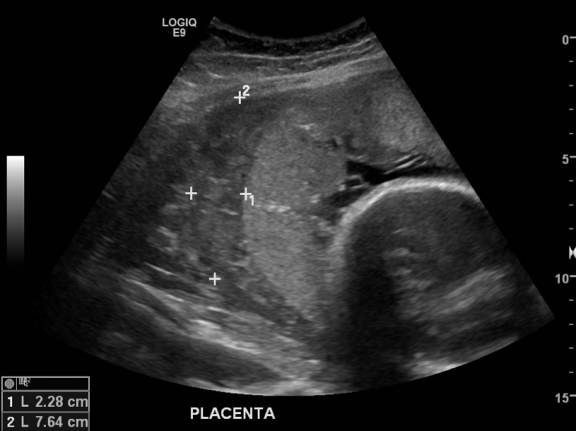

C. This patient’s history of acute onset painful 3rd trimester vaginal bleeding is concerning for placental abruption. She has multiple risk factors for this diagnosis including hypertension, smoking, cocaine use, multiparity, advanced maternal age, and trauma. Ultrasound should be done first to rule out placenta previa as a pelvic exam in that case may precipitate massive hemorrhage! Ultrasound can also be used to evaluate for abruption however it is a poorly sensitive test and therefore cannot definitively rule it out. Keep in mind that not all abruptions present with vaginal bleeding as significant hemorrhage can be concealed behind the placenta. This patient is at risk of hemorrhagic shock, DIC, and fetal demise so obtain large-bore IV access, continuous cardiac and fetal monitoring, and call OBGYN. A type and screen should be sent in anticipation of need for blood transfusion and Rhogam. Also be sure to send a DIC panel as initial fibrinogen levels <200 mg/dL have a nearly 100% positive predictive value for severe postpartum hemorrhage.

Case courtesy of Dr Andrew Dixon, <a href="https://radiopaedia.org/">Radiopaedia.org</a>. From the case <a href="https://radiopaedia.org/cases/14281">rID: 14281</a>